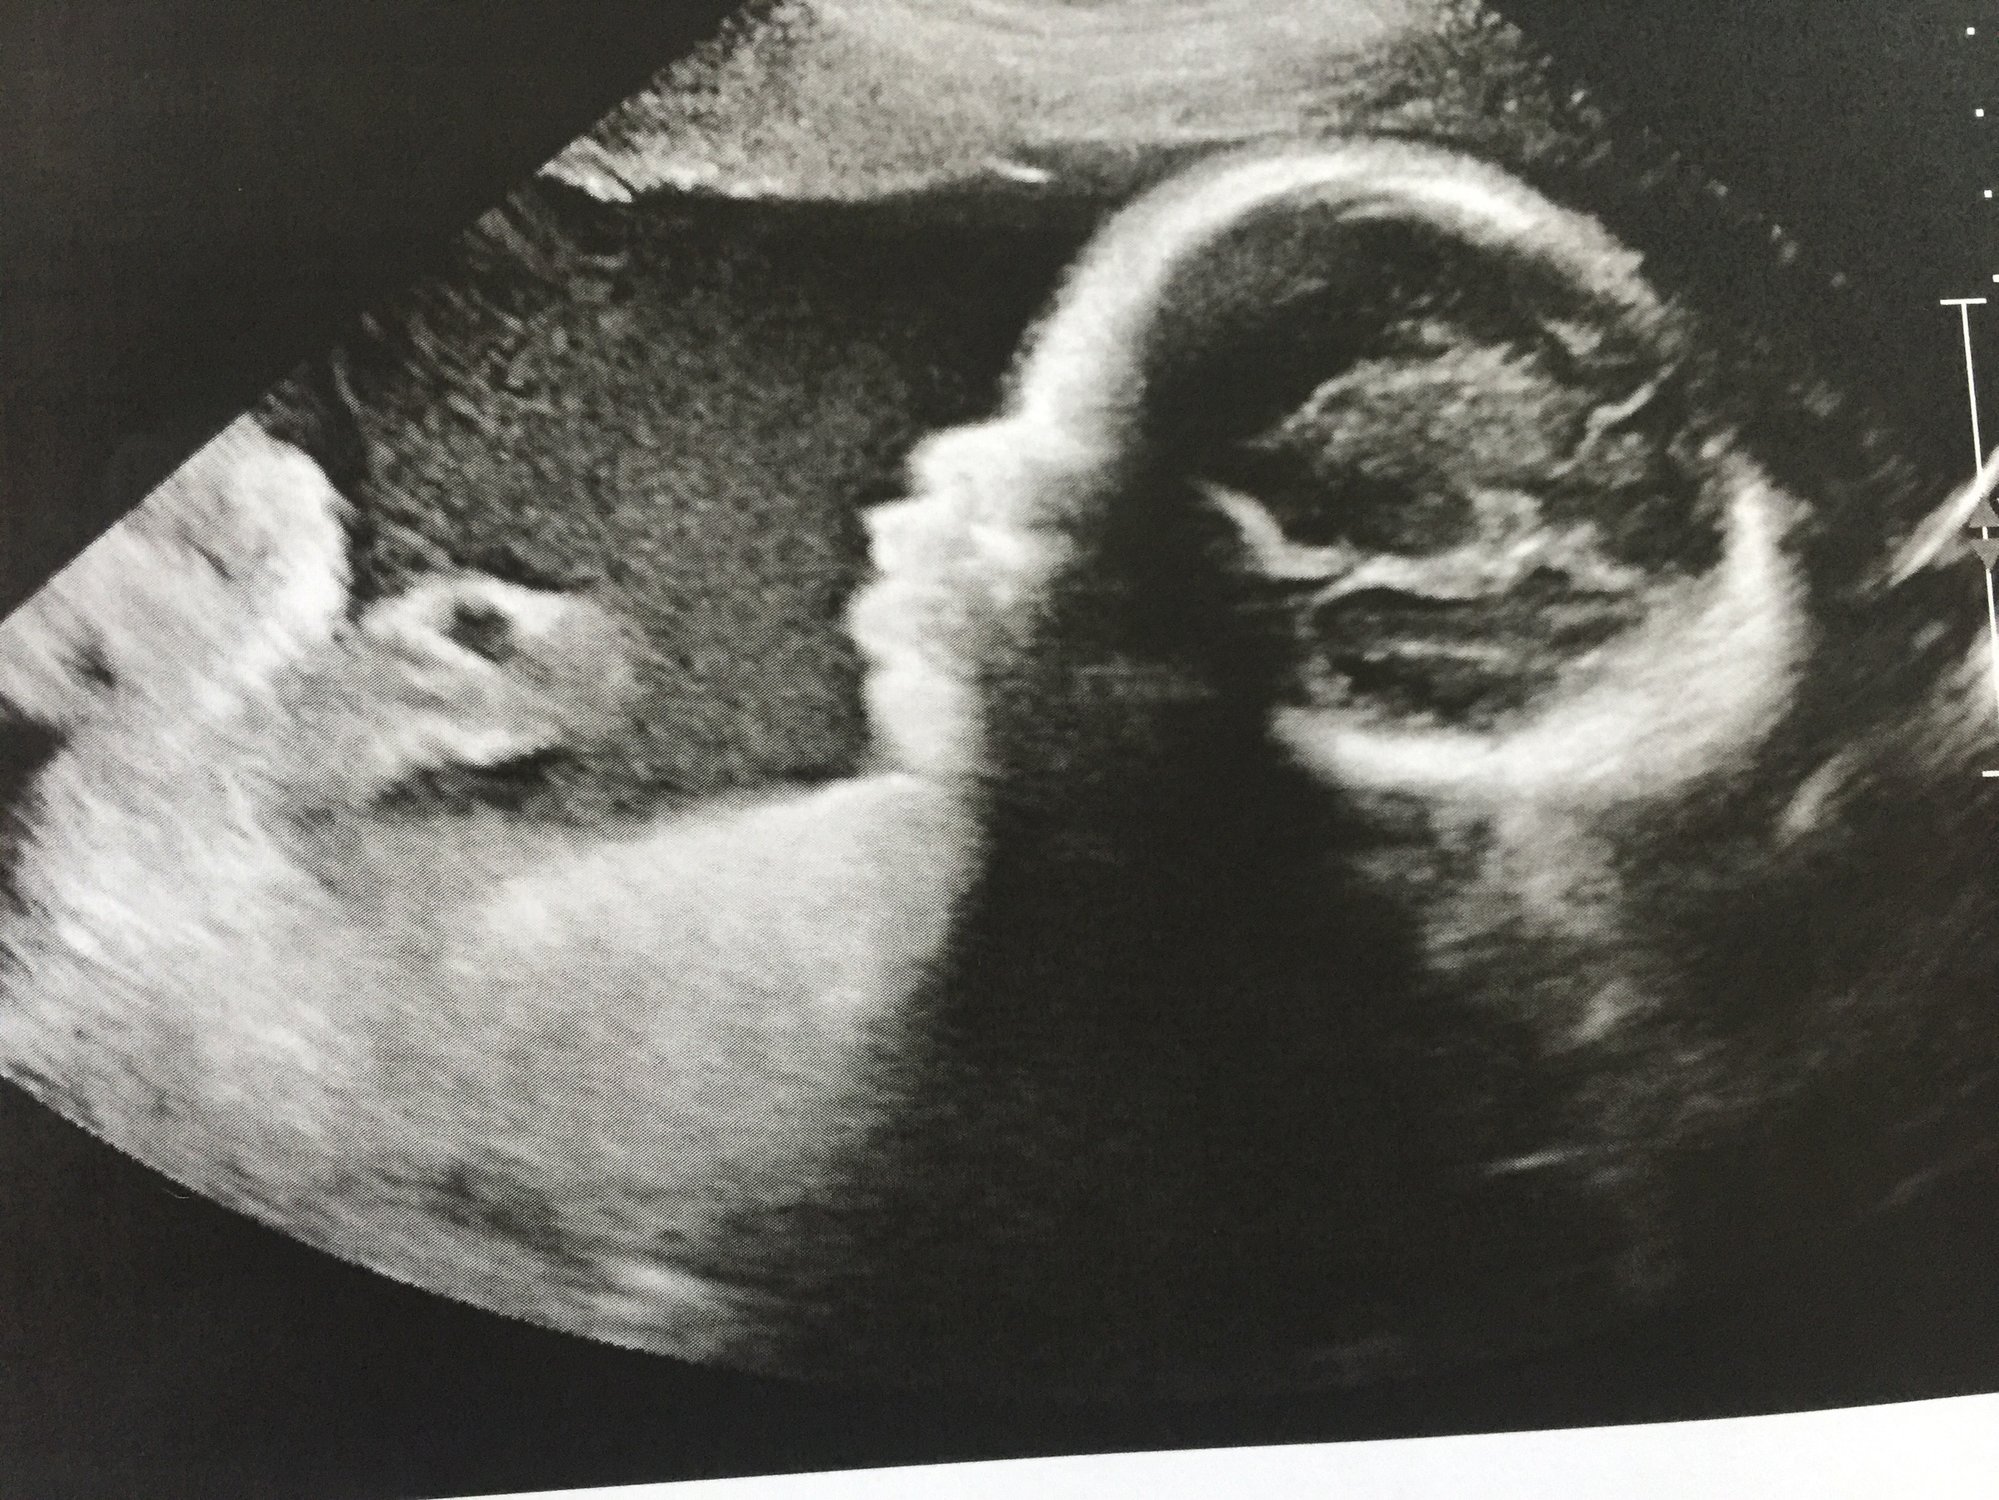

Ladies had my first NST today and it was great babies scored perfect on everything. I also got an ultrasound beforehand and finally got a pick of baby bs profile and a pick of the girls heads. Baby a weighs 3lbs 15 oz and baby b is 4lbs and 6oz crazy the size gap they have always been close in size here are the pics